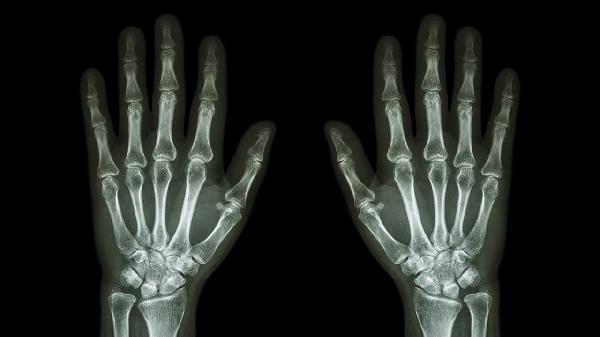

关节软骨退行性变会引发晨僵和活动受限,X线可见关节间隙狭窄。建议减少抓握动作,遵医嘱使用硫酸氨基葡萄糖胶囊修复软骨,疼痛明显时可短期服用洛索洛芬钠片。关节腔注射玻璃酸钠可改善润滑功能。